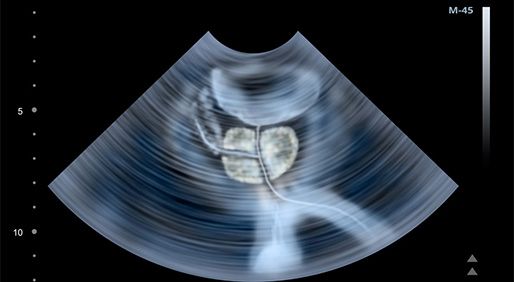

Novel next-generation imaging modalities have greater visibility than conventional imaging tools, leading to higher detection rates and earlier treatment of early recurrences and metastatic disease among men with prostate cancer, explained Hussein Aoun, MD.